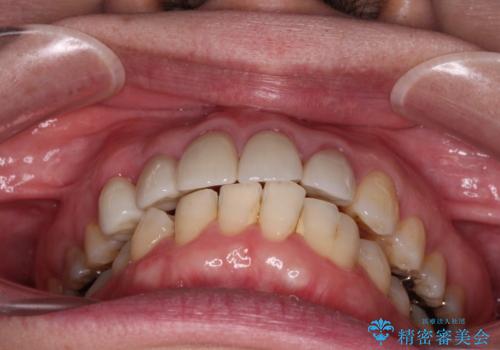

八重歯と形の悪い前歯 矯正治療とセラミック治療

- 長年前歯の歯並びで悩んでいるとのことで来院された患者様です。

機能的なことを考えると八重歯となっている犬歯は抜歯せず、歯列を改善することが望ましいとされますが、数十年もの間犬歯がない咬み合わせで問題なく過ごしてきたため、八重歯を抜歯することで、手っ取り早く歯列を改善することとしました。

また、当初は予定しておりませんでしたが、歯列が整ったことで前歯の歯の色や形が気になり、矯正治療後にオールセラミッククラウンにて補綴治療することとしました。

あっという間に気になっていた歯列が改善され、自然な口元になり、患者様には大変満足していただきました。